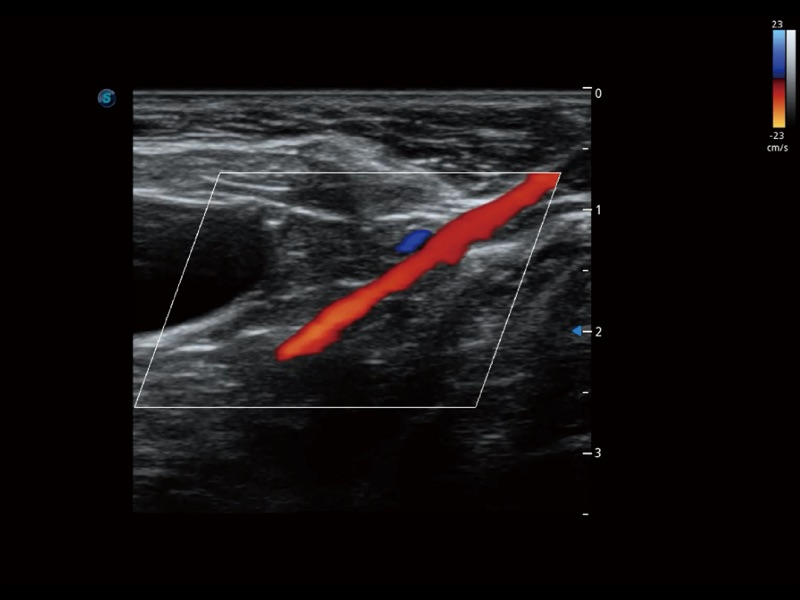

通过创新的 Matrix E自适应滤波器和超长时间域算法,极大提升超低速微细血流的检出能力,同时更精准地滤除软组织和噪声信号,为兽用医生提供以往无法通过常规血流获得的疾病诊断信息。

通过色彩血流和实时宽景相结合,可观察到完整的静脉或动脉的血流,方便医生检查。实时扫查过程中,如有任何操作失误也可以很容易地进行回扫擦除,而不会中断扫查。

为精细结构及组织边缘提供高清晰度的图像和更大的成像视野。帮助减轻医生的用眼疲劳,快速精准获得测量的数据。